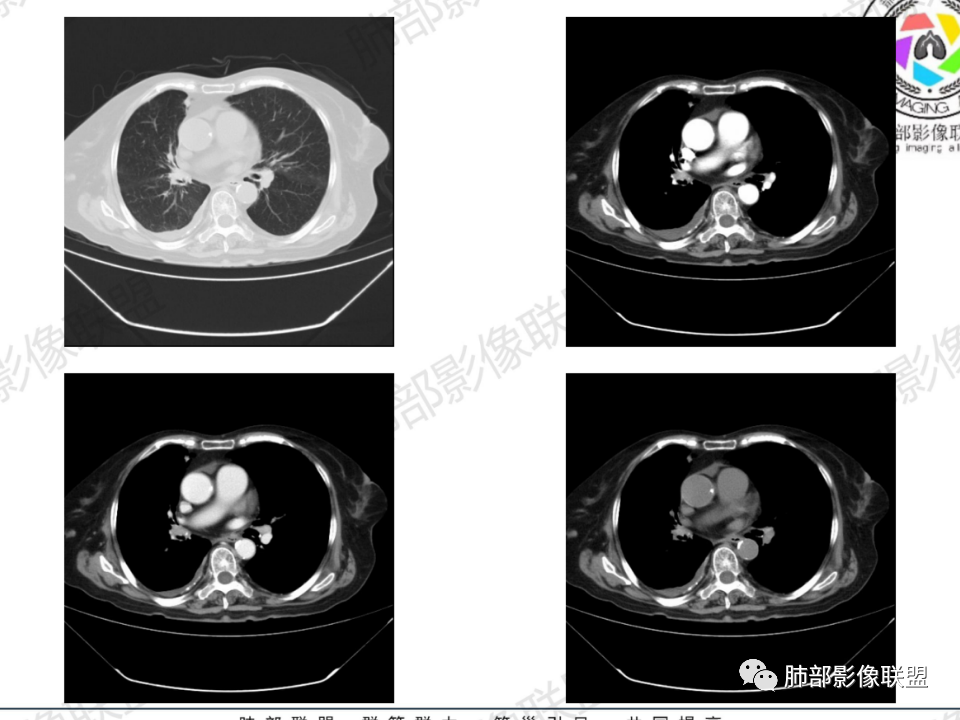

老年患者,病程中等,有咳嗽/喘息/低热症状,肿瘤标志物升高,感染标志物不高,右上肺新生物,中央型,边界清楚,有分叶,支气管截断,内有坏死,不均匀强化,考虑肺癌,鳞癌?

那个人:老年女性,亚急性病程,咳嗽发热。有垂体前叶功能减退,目前激素替代治疗,长期激素,量小,不知道累积量,没有目前激素水平指标。既往有淋巴结结核病史。肿瘤标记物Ca125升高。血沉升高,C反应蛋白轻度异常。影像,右肺上叶靠近肺门团块影,右肺门淋巴结钙化肿大,支气管狭窄,局部增厚,团块影外朝内改变,强化明显,血管破坏不明显,有粘液。和纵隔胸膜分界清楚,周围肺组织有斑片渗出影,右侧胸腔积液,考虑炎性?结核?支气管镜检查除外恶性飞鹰行动:老年患者,影像表现 右肺上叶占位性病变,边界清楚,有分叶征,内见细小钙化,右肺上叶支气管截断,增强病灶不均匀强化,病灶内有条状坏死区(扩张的支气管?),纵膈内未见增大淋巴结,考虑炎性病变,结核可能。一切∮随缘:右肺上叶实性肿块形态不规则,呈三角形,边缘分叶,边界伴有磨玻璃影,近段支气管未见明显显示,可能堵塞,病变平扫密度均匀,增强后可见低密度坏死无强化,周围略强化,右肺下叶散在结节。心包积液,及右侧胸腔积液,临床:有低热,低蛋白血症,肿瘤标记物高,考虑恶性:腺癌,神经内分泌癌(强化偏弱了),淋巴瘤,鉴别:结核红星:老年女性患者右肺上叶,肺门上区 分叶状肿块 ,右肺上叶支气管显示不清,增强扫描肿块,中等程度强化可见小斑片状坏死区,病灶内部可见斑点状钙化灶,病灶周围可见斑片状及小斑点状影,纵膈淋巴结增大,其他区域,胸膜下可见斑点状钙化。考虑肉芽肿性病变,结核的可能性大。老年患者最排除肿瘤性病变腺癌。土娃:右上肺不规则肿块影,边缘分叶,边界磨玻璃影欠清,病灶分叉状,内见点状钙化影及坏死灶,支气管堵塞,病灶增强强化不明显。考虑瘤样结核,鉴别淋巴瘤。张小兵:老年女性,亚急性病程,右肺上叶见不规则肿块,边缘平直凹陷为主,周围GGO边界不清,内见点状钙化及坏死灶,增强持续性渐进强化,右侧少量胸腔积液,双肺门及纵隔肿大淋巴结伴钙化,综合考虑慢性炎症。saf:老年患者,影像表现 右肺上叶占位性病变,边界清楚,有分叶征,增强病灶明显不均匀强化,纵膈内未见增大淋巴结,考虑炎性病变,结核可能。小兜:老年女性,咳嗽喘息一月,发热三天,肿瘤标志物升高,长期激素替代治疗。CT示右肺上叶近肺门不规则实变影,周围伴磨玻璃影,增强持续性渐进强化,内部血管破坏不厉害,内部可见多发条形低密度灶,右侧胸腔可见少量积液,双肺门及纵隔可见钙化淋巴结,考虑为炎性病变,结核可能玫:女,79咳嗽,喘息一月,发热三天入院,右肺上叶不规则形软组织密度肿块影,边界清晰,边缘见分叶及细短毛刺,病灶内见点状钙化影及稍低密度区,病灶边缘呈磨玻璃样改变,增强扫描,病灶呈不均匀性强化,考虑炎性病变,鉴别鳞癌。大雄:老年女性,既往诊断淋巴结结核,提示已治愈,近2年服用激素,诱导结核复燃→发热;纵隔肺门淋巴结肿大钙化,压迫支气管,右肺上中下叶支气管均狭窄→喘息咳嗽;尖段支气管受累闭塞→肺不张、支气管粘液栓;累及胸膜,结核性胸膜炎并胸水→右侧胸痛;实验室,血沉快,CA125高,低蛋白,符合;下一步,支气管镜尖段支气管刷检抗酸染色周太狼:老年女性,亚急性病程,肿瘤标志物升高。CT示右肺上叶尖段不规则肿块影,有分叶、收缩,周围伴磨玻璃影,增强渐进强化,内部可见多发条形低密度灶,右侧胸腔及心包少量积液,纵隔内淋巴结稍增大。倾向于恶性病变,肺癌伴阻塞性炎变可能。丽:老年女性,右肺上叶不规则软组织肿块,边缘清晰,内密度不均,可见点状钙化及粘液栓,周围可见片状高密度影,增强后均匀强化,内多发低密度,纵膈多发钙化淋巴结,考虑结核可能大,建议结合支气管镜检查除外肿瘤宇宙:右胸廓缩小,右肺上叶团块影及不张,平直边,周围磨玻璃影,纤细胸膜牵拉,上叶尖段支气管堵塞,明显延迟强化,可见支气管粘液栓,两肺门钙化淋巴结,右侧胸水,考性炎性肉芽肿,鉴别腺癌王秀仙:右肺上叶肺门区肿块,上叶支气管开口阻塞,形态不规则,密度不均,内可见支气管粘液栓及多发小灶性坏死,周围磨玻璃影边缘模糊,渐进强化,右侧胸腔积液、胸膜钙化,考虑炎性肉芽肿性病变,慢性炎症。鉴别鳞癌,结核。刘丹:老年女性,右肺上叶肿块伴钙化,右肺上叶支气管截断,增强后均匀强化,周边可见点片状模糊影,右侧胸腔积液,右肺门淋巴结增大,考虑占位并阻塞性炎症,肿瘤?结核?建议纤支镜检查。小飞:右肺上叶纵隔旁软组织肿块,边缘深分叶、长毛刺及毛刷样短毛刺,边缘磨玻璃影,磨玻璃边界模糊,支气管截断,平扫密度不均,可见点状钙化,增强不均匀明显强化,心影增大,心包积液,右侧胸腔积液,考虑恶性肿瘤,腺癌?秦化君:右肺上叶不规则分叶软组织密度肿块,边缘清晰,胸膜牵拉,周围花花草草,上叶尖段支气管阻塞,内可见点状钙化,增强后密度不均可见支气管粘液栓及坏死区,内见血管分枝。中间段及中叶,下叶支气管狭窄,壁见钙化。右肺门淋巴结肿大,右侧胸腔积液,心包粘连肥厚。考虑1右上肺恶性病变,鳞癌?2右肺多叶段支气管狭窄,考虑支气管内膜结核?3胸腔积液及肺门淋巴结肿大,转移?风儿:老年女性,右肺上叶肿块,形态不规则,外围大内带小,边缘分叶膨隆平直及毛糙,密度不均,内见支气管粘液栓及多发小灶性坏死,坏死边缘清晰 ,渐进强化,上叶尖段支气管阻塞,叶支气管壁有局限性增厚,邻近胸膜腔微积液;纵隔及双肺门淋巴结肿大,部分钙化,右侧胸腔积液、心包积液、胸膜钙化,考虑炎性,肉芽肿性结核可能性大。鉴别鳞癌,女性及血供均不支持;腺癌,坏死边界太清晰。流心明智:老年女性,79岁,咳嗽、气短1月,发热3天。胸CT:右肺上叶见不规则肿块,边缘有膨隆、有平直凹陷,周围GGO边界不清,病灶内见点状钙化、粘液栓,尖段支气管未见,增强持续性渐进强化,右侧少量胸腔积液,双肺门及纵隔肿大淋巴结伴钙化,肺动脉增粗。考虑:右上叶尖段堵塞并慢性炎症,支气管TB并结石?鉴别Ca

临床信息:老年女性,亚急性病程,咳嗽发热。有激素使用史。既往有淋巴结结核病史。肿瘤标记物Ca125升高。血沉升高,C反应蛋白轻度异常。 影像所见:右侧胸廓相对狭小,右肺上叶不规则团块影贴附纵隔旁,轻度分叶,整体密度较均匀,偶见钙点。

相应上叶尖端及前段支气管开口未能追踪(阻塞),开口处见钙化。病灶渐进性强化,并衬托出较完整尖段及前段含液支气管影。支气管开口区域未见异常高密度强化(如类癌等)及相对乏血供区(如鳞癌)。病灶区未见液化坏死。右上纵隔及胸廓入口区未见病灶胸膜外突破(栽赃)。

右肺上叶后段等区域散在片状影,边界不清(提示渗出性病灶)。

纵隔及双肺门见钙化淋巴结。心包积液,右侧胸腔积液(提示存在活动新病灶)。双侧胸膜下见多发斑点状钙化,胸廓变形(提示存在结核基础病变可能)。 诊断意见:综上,右肺上叶块状影更符合继发性肺结核。 最后小结:既往诊断淋巴结结核,提示已治愈。近2年服用激素,可疑诱导结核复燃,也可引起发热。纵隔肺门淋巴结肿大钙化,压迫支气管,右肺上中下叶支气管均狭窄,所以引起喘息咳嗽。尖段支气管受累闭塞,导致肺不张、支气管粘液栓,出现条状无强化区。病变累及胸膜,导致结核性胸膜炎并胸水,引起右侧胸痛。实验室检查血沉快,CA125高,低蛋白,均符合结核。下一步,建议支气管镜尖段支气管刷检并抗酸染色。(本段摘自於雄老师精彩发言)